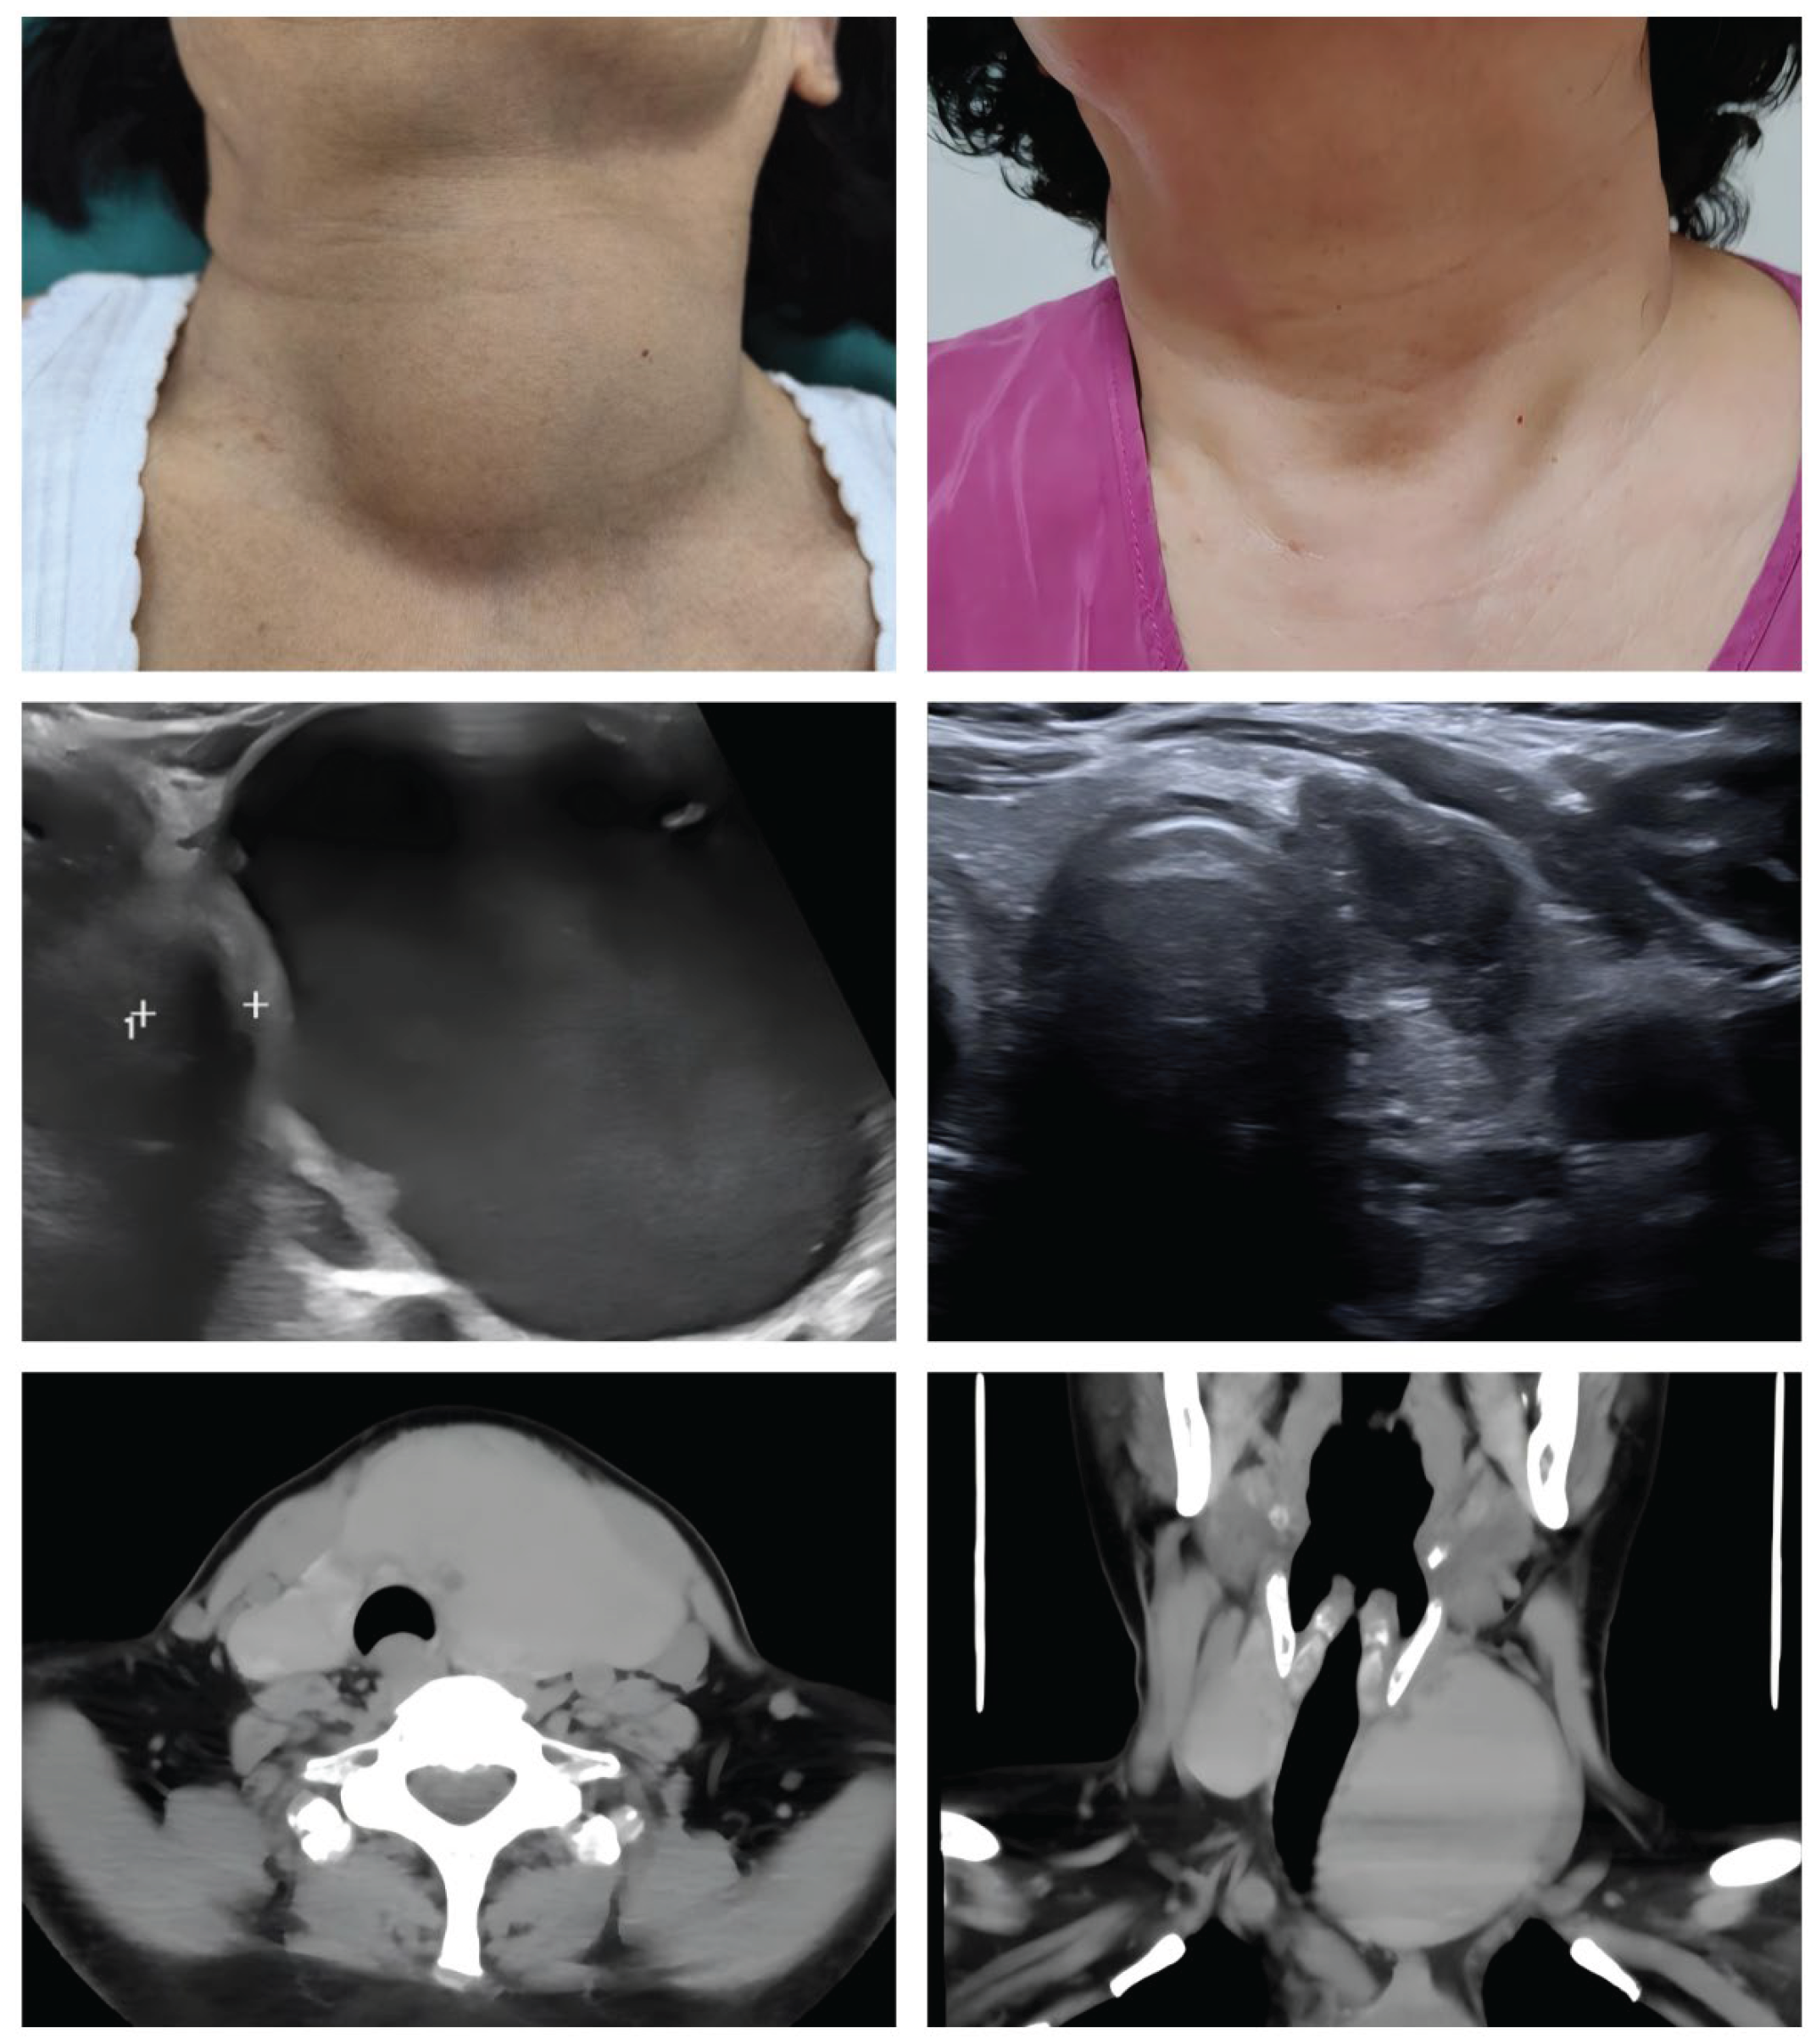

On physical examination, a large and non-tender mass was readily palpable in the left anterior neck, consistent with a large cystic lesion(Figure1A). An ultrasound (US) of the neck was performed, which confirmed the presence of a giant, predominantly cystic lesion originating from the left thyroid lobe (Figure1C). The lesion measured approximately 7x6 cm by US. To better delineate the anatomical relationships and assess the degree of airway compromise, a computed tomography (CT) scan of the neck was obtained. The CT imaging provided a clear depiction of the mass effect, revealing significant rightward deviation and extrinsic compression of the trachea, resulting in noticeable narrowing of the airway lumen (Figure 1E,F). This finding directly correlated with the patient's primary complaint of dyspnea.

At her three-month and one-year follow-up visit, the patient was completely asymptomatic. The dyspnea and neck pressure had fully resolved, and there was no palpable or visible mass in her neck (Figure1B). A follow-up US examination was performed, which demonstrated a dramatic and successful outcome. The previously giant cyst had resolved into a small, irregular, hypoechoic area , showing no evidence of fluid reaccumulation (Figue1D).

Figure 1. Pre- and Post-Treatment Evaluation. (A) Pre-treatment clinical appearance showing a large, bulging mass in the left neck. (B) Clinical appearance at one-year follow-up, showing complete resolution of the mass. (C) Pre-treatment ultrasound examination showing a 7cm, well-defined anechoic area on the left side. (D) One-year follow-up ultrasound showing the original cyst resolved into a small, irregular, hypoechoic area. (E) Pre-treatment axial CT scan showing the giant cyst causing significant tracheal compression and rightward deviation. (F) Pre-treatment coronal CT showing a giant mass in the left thyroid, causing tracheal compression and narrowing.